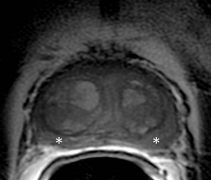

Figure 2 is biopsy proven prostate adenocarcinoma in a 62-year-old man with a Gleason grade of 6 (3+3). This example shows how functional imaging can help identify the tumor.

Figure 2a: Axial T2-weighted image at the level of the mid gland shows nonspecific low signalbilaterally in the peripheral zone(asterisks) with minimal capsular bulge on the left.